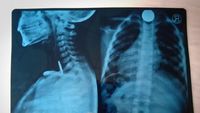

Noverius Gulo (4) menelan uang logam saat tengah bermain dengan saudaranya. Noverius harus menjalani operasi meskipun kondisi keuangannya tidak memungkinkan.